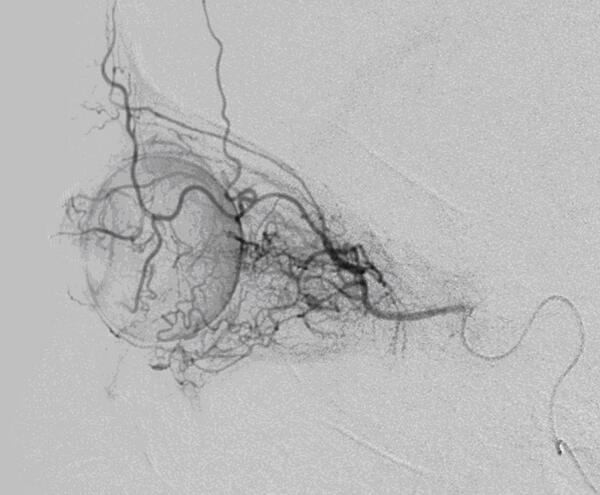

3.超选眼动脉介入灌注美法仑治疗眼内期视网膜母细胞瘤(RB)技术要点:(1)路径选择:超选介入动脉内灌注化疗技术的核心目的是通过微导管超选患侧眼动脉血管,将化疗药物缓慢灌注至眼动脉内,经眼动脉的视网膜中央动脉等肿瘤供血动脉进入肿瘤组织,在肿瘤局部形成高血药浓度,而不会有大量化疗药物进入全身血液循环。A.颈内动脉-眼动脉型:大多数病例采用的路径,微导管在微导丝引导下放置于眼动脉开口处或进入眼动脉开口。B.颈外动脉-眼动脉:在眼动脉纤细或闭塞的病例中采用。其中比较常用的途径为颈外动脉-脑膜中动脉/脑膜副动脉-眼动脉。(2)微导管到位标准:微导管到位后,透视下使用1ml注射器缓慢沿微导管推注造影剂,推注过程中见眼动脉及其分支显影,脉络膜染色均匀,且未见造影剂逆流至颈内动脉或颈外动脉其他分支,说明微导管到位理想。化疗药物灌注完毕后,重复以上操作,明确微导管未移位,如移位则可考虑追加化疗药物(图2)。(3)化疗药物选择、剂量、灌注方式及疗程:美法仑(Melphalan)的化学名称为左旋苯丙氨酸氮芥,是一种细胞周期非特异性药物,主要用于多发性骨髓瘤、乳癌和卵巢癌的治疗,主要副作用为抑制骨髓,近年来用于内视网膜母细胞瘤介入化疗[5-7]。美法仑药物剂量大小与采用的路径类型相关,A路径美法仑剂量为6~8mg/眼/次,B路径美法仑剂量8~10mg/眼/次。药物采用输液泵持续泵入,泵入时间大于30min。一次化疗后1个月复查化疗效果,根据检查结果决定是否继续超选介入动脉内灌注化疗治疗。(4)患儿介入安全注意事项:限制患儿造影剂总剂量在4ml/kg体重(威视派克320);注意放射线防护,尽可能使用小视野,低X线剂量,限制透视时间,降低脉冲(3~6fps),使用铅衣遮挡性腺。(5)操作步骤:静脉麻醉,1%利多卡因局部逐层皮下及股动脉鞘周围浸润麻醉,以Seldinger技术穿刺右股动脉,见到鲜红搏动性出血后,经穿刺针置入导丝,置入动脉鞘时应保持动脉鞘旋转进入,置入后贴膜固定。4F单弯造影导管行常规患侧颈内、颈外动脉造影,根据造影结果选择治疗路径。微导管在微导丝引导下根据微导管到位标准放置到位,配药及药物泵注。

1.治疗效果:本组53例患儿(65只患眼)中,14例18眼行1次化疗,35例43眼行2次化疗,4例4眼行3次化疗,累计行超选眼动脉介入灌注美法仑治疗116例次,其中A途径98例次,B途径18例次,手术技术成功率100%。53例患儿65只患眼中,55只患眼肿瘤不同程度缩小,有效率84.6%(图3),10只患眼因肿瘤进展而行眼球摘除(15.4%)。未行眼球摘除的55只患眼随访至今,均未发现疾病进展。